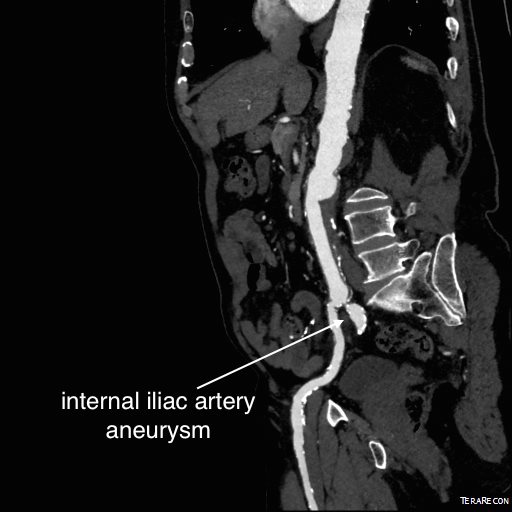

For example, take this patient who after EVAR of aortic aneurysm with AFX developed metachronous dilatation of the common iliac artery to 3.9cm with abdominal pain. The average diameter is 18.5mm. From the table, that rounds to 19mm corresponding to 283.53 square mm. If the internal iliac artery requires a 13mm graft, that is 132.73 square mm, the difference being 150.80 square mm. That corresponds to a 14mm diameter graft, but a slightly larger graft is preferred for oversizing. The external iliac artery is 8mm, and putting a 13mm Viabahn (largest available) in that would result in the B-infolding in the 8mm external iliac. Here, I bailed myself out by simply placing a 20mm AFX iliac limb extension, which by virtue of its design is resistent to infolding and tolerant of parallel grafts laid alongside in constricted channels. I found that the AFX iliac limb, a 20-13mm x 88mm length extension well suited for this.

The AFX graft limb seems to adapt to the presence of the parallel “sandwich” graft which is deployed second and ballooned last. In followup, there was shrinkage of the common iliac artery aneurysm sac and no endoleak.